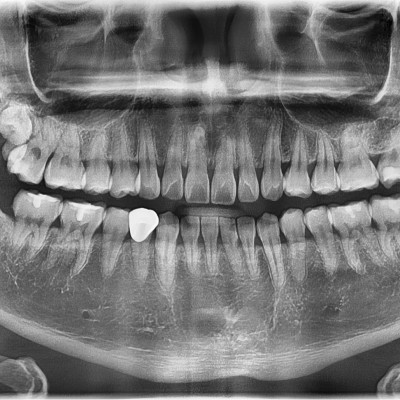

#28,38 사랑니 발치 #28,38 사랑니 발치 구강 외과 전문의가 당일 발치했습니다. --------------------------..